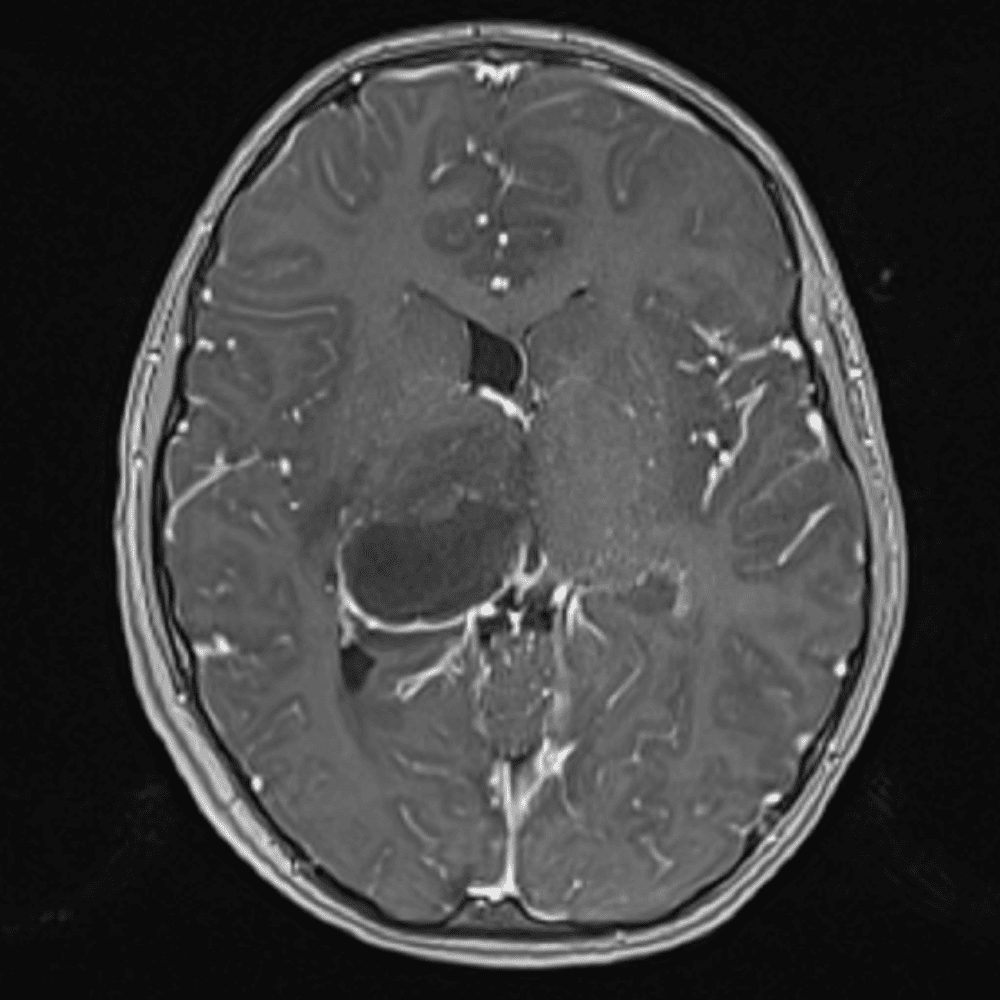

๋‹น์ง ์‹œ ํ”ํžˆ ๋ณผ ์ˆ˜ ์žˆ๋Š” ์‚ฌ๋ก€์˜ ์ „ํ˜•์ ์ธ ์˜ˆ๋ฅผ ํฌํ•จํ•ฉ๋‹ˆ๋‹ค.

39 ์‚ฌ๋ก€

์—ฐ์Šต

๋ฏธ๋ฌ˜ํ•˜๊ฑฐ๋‚˜ ์–ด๋ ค์šด ์‚ฌ๋ก€์™€ ์ผ๋ถ€ ์ •์ƒ ์‚ฌ๋ก€๋ฅผ ํฌํ•จํ•˜์—ฌ ๋‹น์ง์„ ์‹œ๋ฎฌ๋ ˆ์ด์…˜ํ•ฉ๋‹ˆ๋‹ค.

50 ์‚ฌ๋ก€